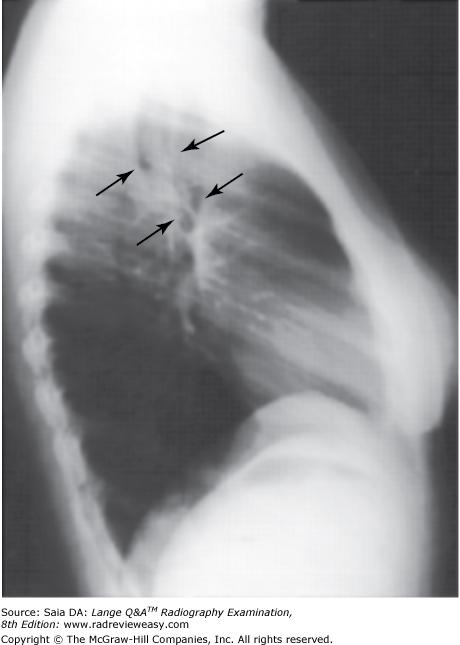

Which of the following statements is (are) true regarding the radiograph shown in Figure 6–16?

- The part is rotated.

- The patient is not shielded correctly.

- There is excessive receptor exposure.

A 1 only

B 2 only

C 1 and 2 only

D 1, 2, and 3

-The patient is well positioned; the spinous processes and sternum are seen clearly without superimposition. Adequate penetration and long-scale contrast are present without excessive receptor exposure. The patient had been shielded properly for the PA projection, but the shield was not moved to the correct location prior to the lateral exposure.